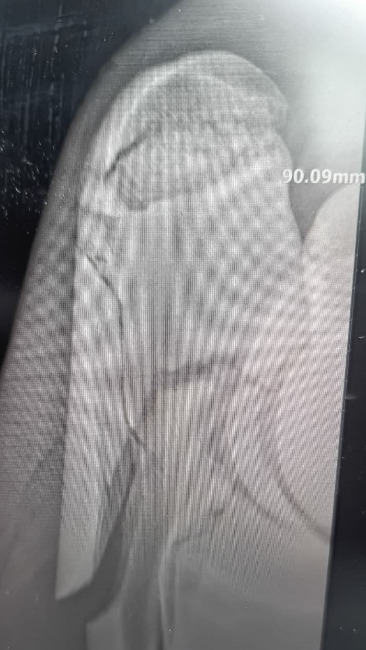

Dzięki Waszej pomocy operacja Zuzi zakończyła się sukcesem. Klacz bezpiecznie opuściła klinikę i obecnie przebywa w pensjonacie dla koni, gdzie jest pod stałą opieką i spokojnie dochodzi do siebie po zabiegu.

Do połowy lutego Zuzia musi mieć ściśle ograniczony ruch — pozostaje zamknięta w boksie, aby kość mogła się prawidłowo zrosnąć. Po tym czasie zaplanowana jest kontrola lekarska. Jeśli badania potwierdzą, że wszystko goi się prawidłowo, Zuzia zacznie bardzo ostrożne wdrażanie do stępa.